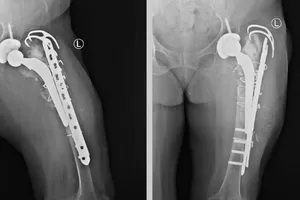

Lần đầu ở miền Trung - Tây Nguyên thay khớp háng và xương đùi bằng Megaprosthesis Y tế - Sức khỏe 24/06/2025 20:55